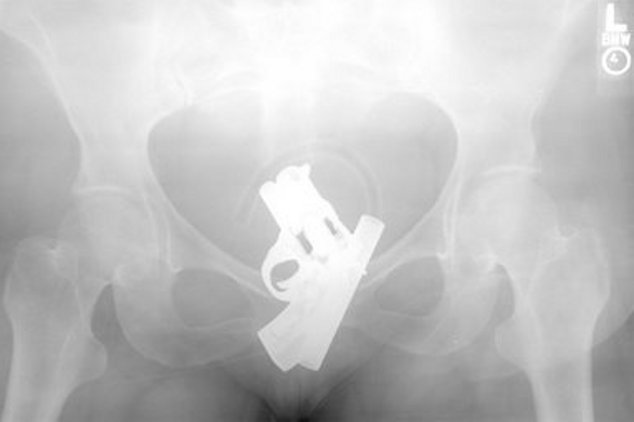

Sinar X adalah teknologi mutakhir yang memudahkan para dokter untuk melihat isi tubuh manusia tanpa harus membedahnya. Bukan hanya organ yang kelihatan, kadang-kadang para dokter juga menemukan perkakas seperti kunci mobil, ponsel hingga botol minum yang terjebak di dalam tubuh pasien. (Foto: Pool)![]() Nicholas Holderman, seorang laki-laki asal Kentucky mengalami cedera fatal saat terjatuh. Kunci mobil yang dipegangnya menancap di wajah, menembus kelopak mata dan tulang tengkorak hingga ke otak. Beruntung, tidak ada kerusakan permanen yang dialaminya. (Foto: The Times) ![]() Laki-laki 60 tahun asal Multan, Pakistan mendatangi Nishtar Hospital dengan keluhan yang agak janggal, sejanggal hasil pemindaian dengan sinar X. Sebotol minuman bersoda merek Pepsi terjebak di anusnya, konon dimasukkan secara paksa oleh seorang penjahat yang kepergok akan mencuri 2 ekor sapinya. (Foto: Reuters) ![]() Fateh Mohammad, seorang napi di Pakistan mengaku tidak tahu apa-apa saat bangun pagi dan merasa ada yang tidak nyaman di anusnya. Mungkin ada teman satu sel yang jahil, hasil pemindaian dengan sinar X menunjukkan ada bohlam lampu pijar terjebak di anusnya. (Foto: Typepad) ![]() Lewat pemindaian dengan sinar X, tim dokter di di El Savador menemukan sebuah ponsel di usus halus. Pasien yang merupakan anggota geng Mara Salvatrucha merupakan 1 dari 4 napi yang berusaha menyelundupkan ponsel ke penjara namun gagal karena setelah ditelan ponsel tersebut tidak bisa keluar lagi. (Foto: CBS News) ![]() Tim bedah kandungan di sebuah rumah sakit panik saat foto sinar X menunjukkan ada pistol terjebak di vagina seorang pasien, dengan posisi seperti sudah terkokang dan siap ditembakkan. Operasi dilakukan dengan rompi antipeluru, tapi setelah dikeluarkan ternyata hanya korek gas yang bentuknya mirip pistol. (Foto: Neatorama) Sumber : http://health.detik.com/readfoto/2012/09/03/100214/2005786/1406/5/yang-horor-dari-sinar-x#viewfoto |